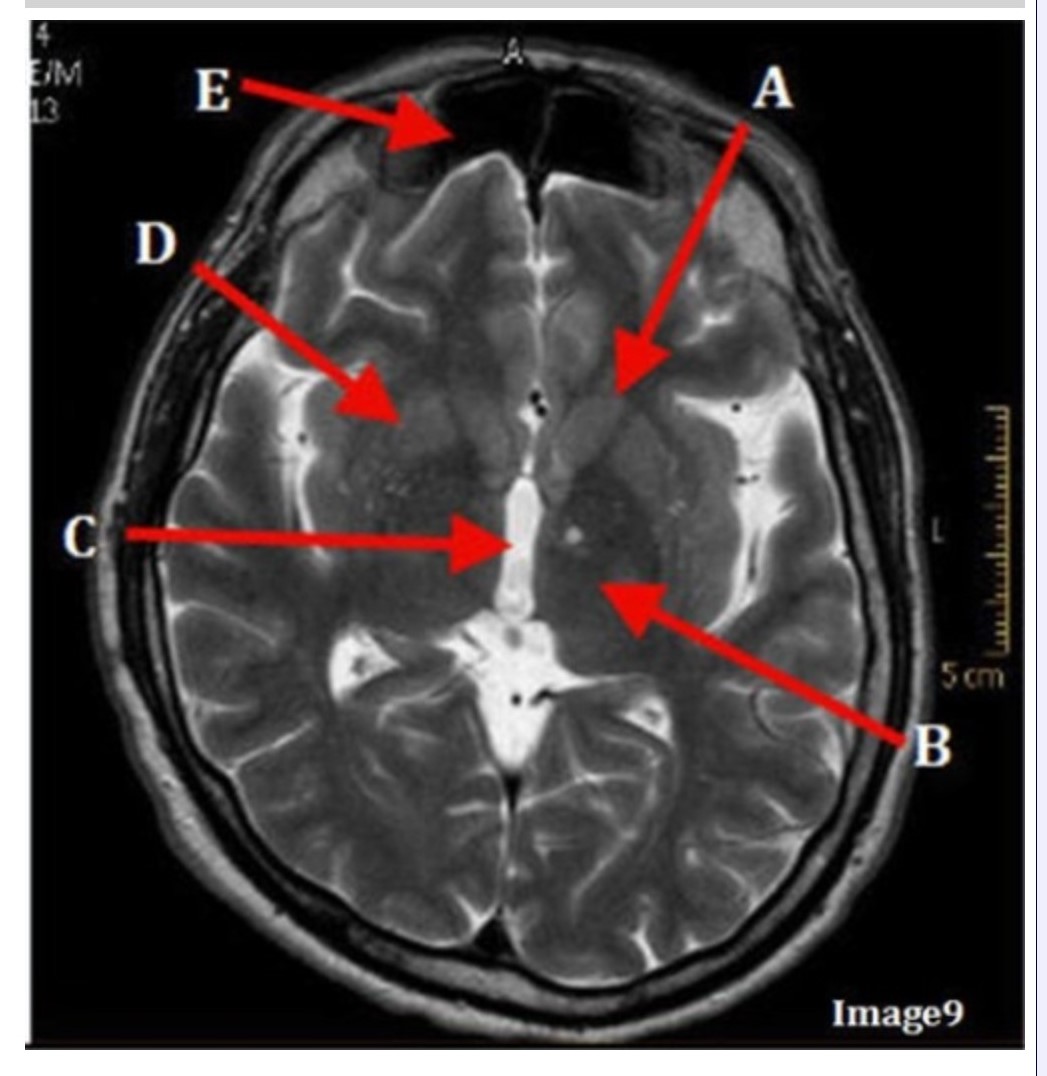

Letter C in Image 9 is pointing to:

A. Third ventricle

B. Thalamus

C. Lentiform nucleus

D. Caudate nucleus

Letter B in Image 9 is pointing to:

A. Third ventricle

B. Thalamus

C. Lentiform nucleus

D. Caudate nucleus

Letter D in Image 9 is pointing to:

A. Third ventricle

B. Thalamus

C. Lentiform nucleus

D. Caudate nucleus

Letter E in Image 9 is pointing to:

A. Maxillary sinus

B. Sphenoid sinus

C. Frontal sinus

D. Ethmoid sinus

Letter A in Image 9 is pointing to:

A. Third ventricle

B. Thalamus

C. Lentiform nucleus

D. Caudate nucleus

Image 9 is an example of a _____ weighted sequence acquired in the _______ scan plane.

A. T1; Axial

B. T2 FLAIR; Sagittal

C. T2; Axial

D. T2; Coronal